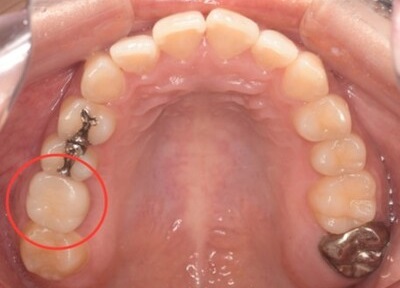

抜歯予定の歯と移植予定の歯

右上6抜歯後

右上6(青丸)を抜歯し、右下8(赤丸)を移植することを計画した。

右上の抜歯後の治癒を待つため、抜歯の1ヶ月後に移植を行うこととした。